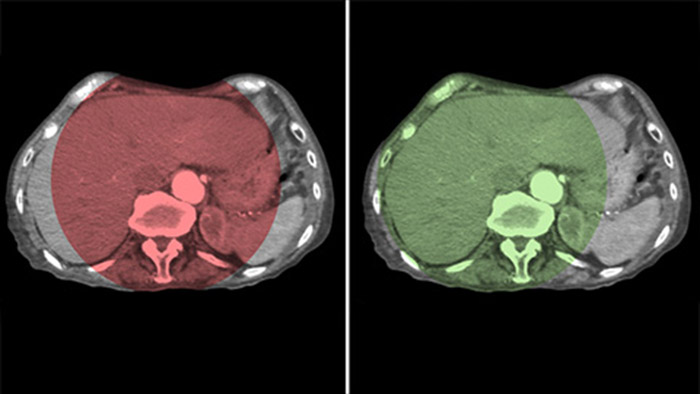

Функция CBCT Dual обеспечивает получение данных артериальной фазы в режиме 3D для визуализации сосудистых структур и данных постартериальной (отсроченной) фазы для визуализации накопления контрастного вещества посредством одного автоматического шага5.

Функция Dual View позволяет одновременно просматривать два набора данных КТ-подобных изображений. Артериальная и отсроченная фазы могут отображаться рядом друг с другом или в виде объединенного наложения.